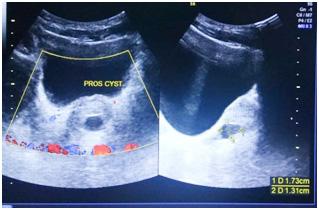

Ultrasound studies : Ultrasound showed cystic lesions in 17 patients and solid masses in three. Medial locations of a cystic retro-vesical mass were consistent with a prostatic utricle cyst (Fig 1) or abscess (Fig 2). Transrectal ultrasound was performed

additionally in eight patients to confirm the intraprostatic or extra-prostatic location of the cysts. Ultrasound revealed mixed echogenic masses in all the three patients with retro-vesical teratoma (Fig 3) which was difficult to differentiate from haematoma and four patients had cystic lesion contained hyperechoic material consistent with dermoid cyst but one letter on confirm on HPE was mullerian duct cyst with cystadenoma. A cystic extra-prostatic mass lateral to

the bladder neck was demonstrated on ultrasound for all seminal vesicle (Fig 4).

Fig 4 — USG images of seminal vesicle cyst Fig 1 — USG images showed prostatic cyst Fig 3 — Radiological images of Teratoma (case no 5)

Fig 2 — Radiological pictures of Epidermoid cyst (case no 3) and Last MRI picture showed b/l seminal vesicle cyst (case no 4)